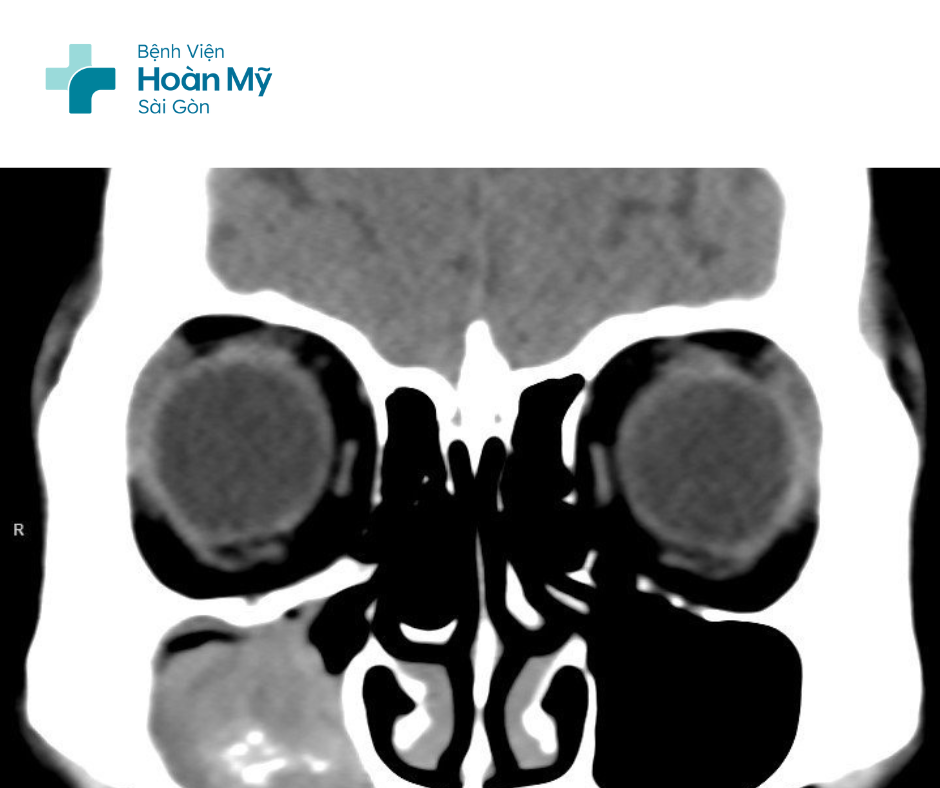

Sau khi khai thác bệnh sử và nội soi mũi cho người bệnh, bác sĩ chuyên khoa Tai Mũi Họng nhận định đây là một bệnh lý nặng và cho người bệnh chụp MSCT mũi xoang. Kết quả cho hình ảnh mờ toàn bộ cùng nhiều nốt cản quang bên trong xoang hàm và xoang sàng phải, sau hội chẩn, các bác sĩ chẩn đoán viêm xoang do nấm và người bệnh được lên lịch phẫu thuật nội soi chức năng mũi xoang vào ngày hôm sau.

Kết quả hình ảnh CT cho hình ảnh mờ toàn bộ cùng nhiều nốt cản quang bên trong xoang hàm và xoang sàng phải.